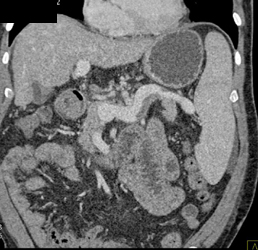

Splenorenal Shunting Due to Portal Hypertension